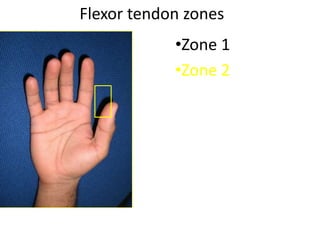

- It describes flexor tendon zones, extensor compartments, and pulley system anatomy.